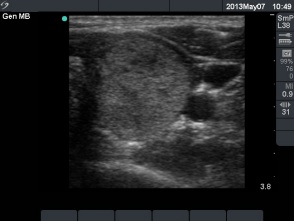

First session of sclerotherapy (1st row of images)

Clinical presentation: a 27-year-old woman was referred for evaluation of a multinodular goiter. The lesion in the left lobe has increased in the past two years and caused neck discomfort.

Palpation: a not firm nodule in the left lobe.

Functional state: euthyroidism with TSH 0.93 mIU/L, FT4 14,3 pM/L.

Ultrasonography: the thyroids were echonormal. There was a small lesion with a maximal diameter of 7 mm in the right lobe and a larger nodule in the left lobe. Both were echonormal.

Aspiration cytology resulted in benign colloid goiter.

We suggested surgery because of the compression signs. The patient told us that she is a cook in a seafarer and she has the opportunity to miss from the work only for a couple of weeks in the subsequent years. We advised ethanol sclerotherapy. Six sessions of ethanol was given. A total amount of 13.7 mL ethanol was administered in six session in 5 weeks.